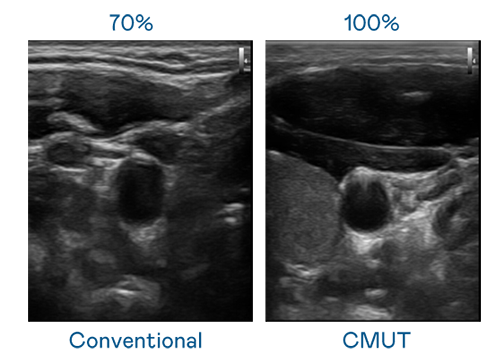

CMUT 技术是一种用电容式微机电元件来产生超音波讯号的技术。与传统 PZT 压电式技术相比,CMUT 频宽增加 30%,更宽频的超音波讯号让影像解析度大幅提升,是实现高影像品质医疗超音波扫描、促进精准医疗发展的关键技术。

超音波影像的解析度高低,首先取决于探头能发出的讯号频宽。9001cc 以诚为本 CMUT 可提供高清晰的超音波讯号,提供高频宽、高灵敏度、影像纹理细节更高的超音波影像,协助医护人员缩短影像判读时间及利用精准的医疗影像进行诊断。